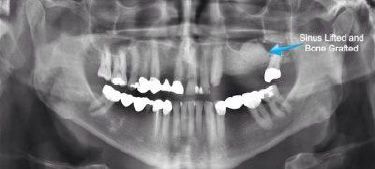

A sinus lift, also called sinus augmentation, is a procedure that makes it easier toplace dental implants. For patients that suffer from bone loss and cannotwithstand implants, it is the optimal procedure and provides needed support.

This procedure increases the amount of bone in the upper jaw that is required fordental implants and is one of the most common bone grafting procedures fordental implant patients.